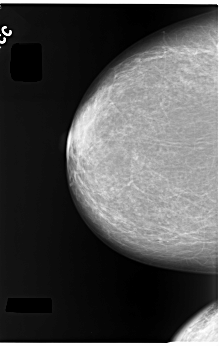

C_0055_1.RIGHT_CC

RIGHT_CC LINES 5880 PIXELS_PER_LINE 3712 BITS_PER_PIXEL 12 RESOLUTION 50 NON_OVERLAY